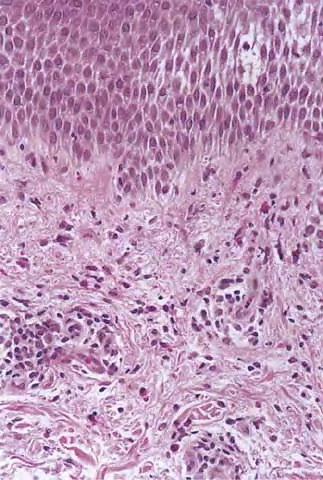

Subacute contact dermatitis = التهاب الجلد بالتماس تحت الحاد